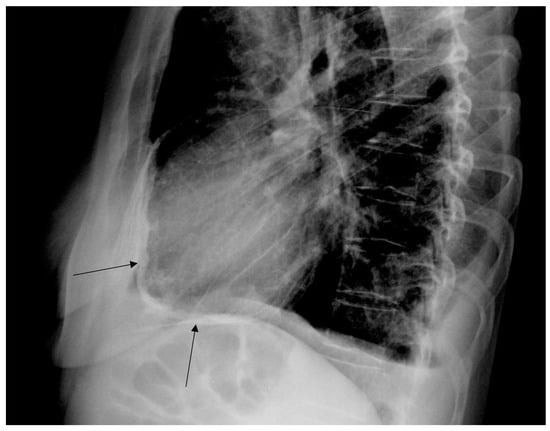

Cardiac Post-Chest Radiotherapy Complications in a 50-Year-Old Patient with Hodgkin Lymphoma

2. Case Report